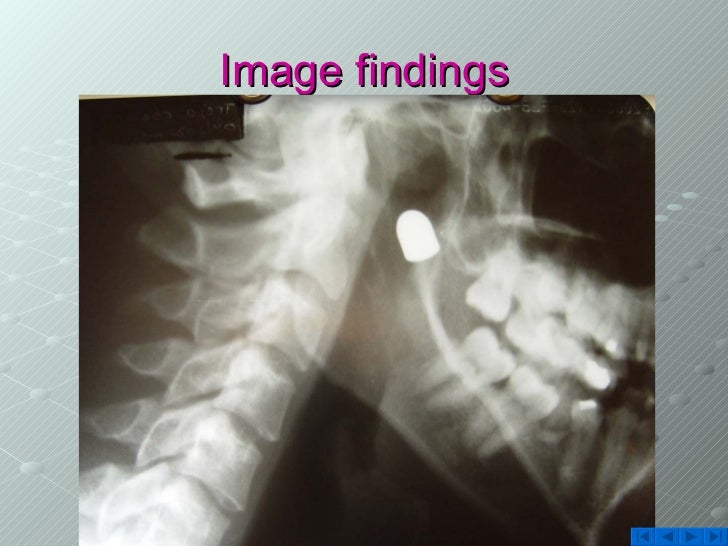

From www.slideshare.net

Gunshot Injury Rare Presentation Gunshot Orthobullets upper extremity gunshot wounds result in notable morbidity for the orthopaedic trauma patient. Wound ≤1 cm, minimal contamination or muscle damage. in the current review, the authors point out key aspects and principles requiring attention when treating low energy. Wound care is determined by. [11][12] damage may include bleeding,. Gun shot wounds are high energy injuries that contribute. Gunshot Orthobullets.